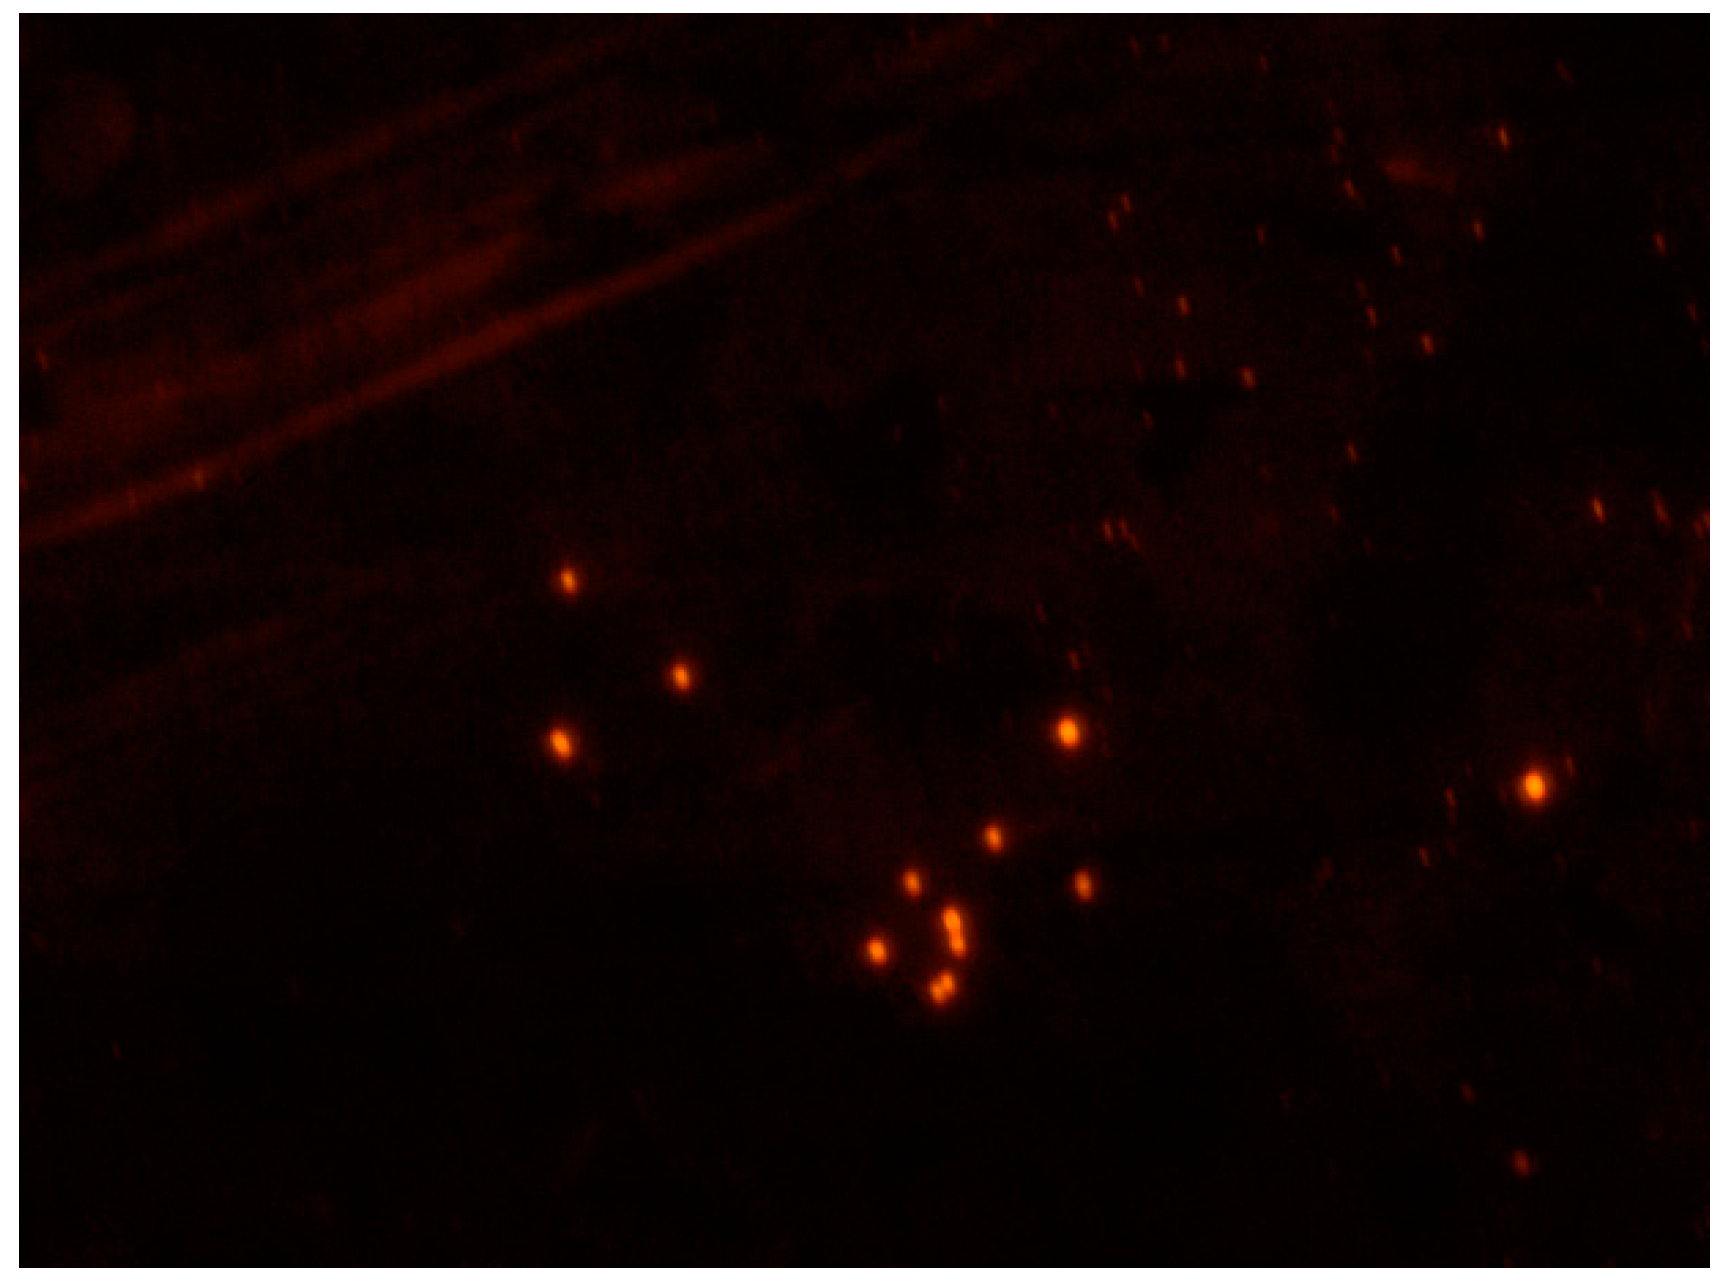

3.2. Characterization of Fluorescent Sunitinib Molecularly Imprinted Polymer (SUT-MIP)